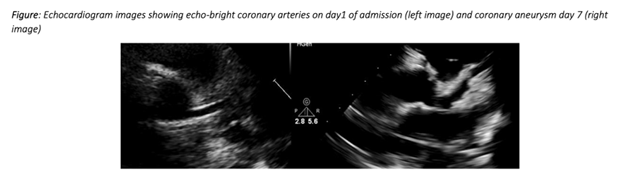

【医学界|必读|全球医学界非常担忧新冠病毒感染儿童和学生】纽约市公共卫生机构报道了纽约儿童新冠病毒患者的案例 , 对比在英国伦敦发生的儿童青少年新冠病毒患者案例:临床症状类似川崎病 , 但又不完全一致 , 包括多器官损伤和炎性感染症状 。